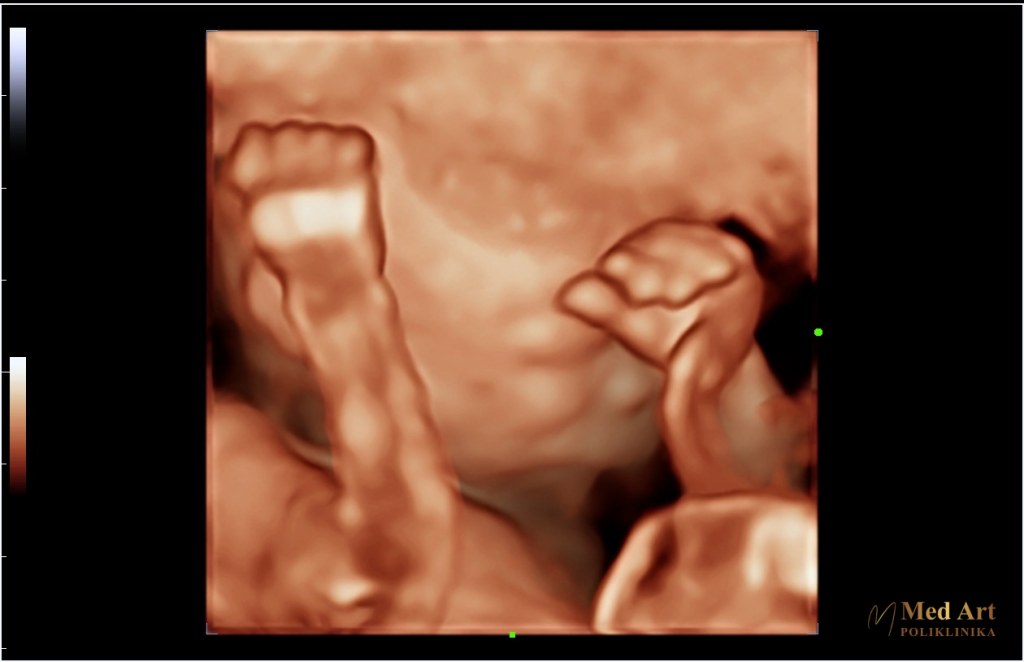

Naglasak je na analizi srca, lica, mozga i kralješnice koji se na ultrazvučnim aparatima 3D/4D/5D tehnologije mogu bolje analizirati pomoću posebnih aplikacija. Mjeri se opseg glavice (HC), biparijetalni promjer (BPD), opseg trbuha (AC) i duljina bedrene kosti (FL). Preko tih parametara se prati rast fetusa prilikom svakog ultrazvučnog pregleda.

Digitalne fotografije ultrazvuka

Poliklinika Med Art među rijetkima pruža trudnicama mogućnost primanja originalnih digitalnih fotografija ultrazvuka u boji….